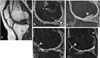

Autologous chondrocyte implantation for cartilage repair: monitoring its success by magnetic resonance imaging and histology

Autologous chondrocyte implantation is being used increasingly for the treatment of cartilage defects. In spite of this, there has been a paucity of objective, standardised assessment of the outcome and quality of repair tissue formed. We have investigated patients treated with autologous chondrocyte implantation (ACI), some in conjunction with mosaicplasty, and developed objective, semiquantitative scoring schemes to monitor the repair tissue using MRI and histology. Results indicate repair tissue to be on average 2.5 mm thick. It was of varying morphology ranging from predominantly hyaline in 22% of biopsy specimens, mixed in 48%, through to predominantly fibrocartilage, in 30%, apparently improving with increasing time postgraft. Repair tissue was well integrated with the host tissue in all aspects viewed. MRI scans provide a useful assessment of properties of the whole graft area and adjacent tissue and is a noninvasive technique for long-term follow-up. It correlated with histology (P = 0.02) in patients treated with ACI alone.